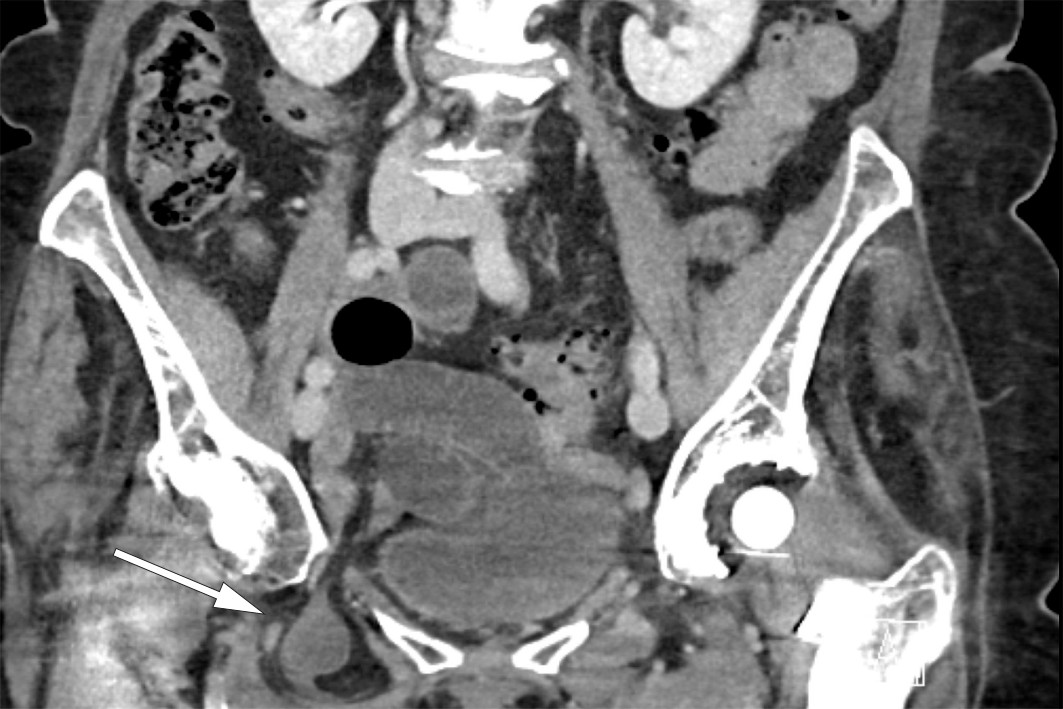

På bildet sees et inkarserert obturatorhernie under laparoskopi. Obturatorhernier er sjeldne og representerer mellom 0,07 og 1 % av alle bukhernier (1, 2). Som regel er det tynntarmen som hernierer gjennom den 2–3 cm lange og 1 cm brede obturatorkanalen i bekkenet. Brokket opptrer oftest hos eldre kvinner, og fordi åpningen på venstre side er beskyttet av sigmoideum, er det vanligst på høyre side. Selv om tilstanden er sjelden, har inkarserert obturatorhernie den høyeste dødeligheten (13–70 % dødelighet i ulike studier) av alle bukveggshernier (1, 2). Symptomene er ofte uspesifikke med magesmerter i nedre høyre del av buken, som en sjelden gang kan palperes som en oppfylning medialt på låret. CT er et viktig supplement i utredningen, og funn av tynntarm mellom musculus pectineus og musculus obturatorius er diagnostisk. Behandlingen er kirurgisk, og både åpen og laparoskopisk tilgang er beskrevet. Laparoskopisk kirurgi gir mindre postoperative smerter, færre postoperative komplikasjoner og kortere sykehusopphold (1).

En sprek kvinne i 80-årene kom inn til sykehus med få timers sykehistorie med akutt innsettende og sterke magesmerter i nedre høyre del av buken. Ved undersøkelse var hun palpasjonsøm i samme område. Hun var tydelig smertepåvirket, men vitale tegn var normale. Blodprøver var alle innenfor referanseområdet. CT abdomen viste et høyresidig obturatorhernie med inkarserert tynntarm og begynnende preobstruktiv tarmdilatasjon (se CT-bilde). Pasienten ble først laparoskopert, og det inkarsererte tynntarmssegmentet og brokksekk ble reponert inn i bukhulen. Tarmen var viabel. Funnet var typisk for inkarserert tynntarm i et obturatorhernie. Det ble deretter lagt inn et preperitonealt nett ved hjelp av total ekstraperitoneal plastikk (TEP). Pasienten ble sendt hjem i velbefinnende første postoperative dag.